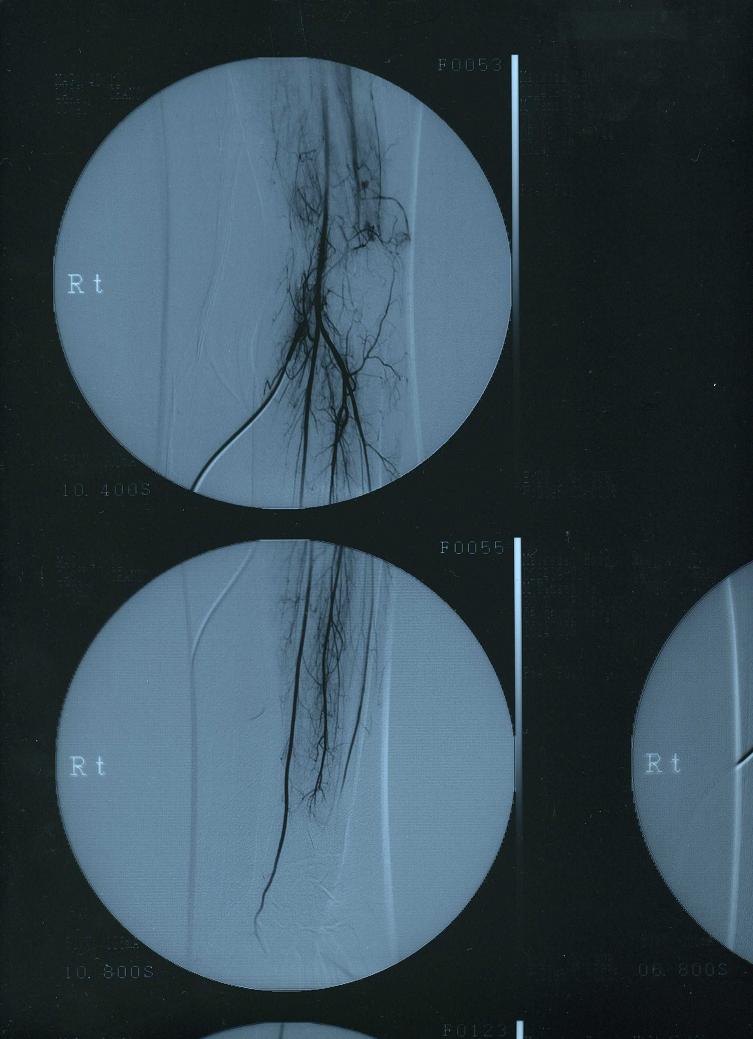

そして、初めてカミングアウトする病気は…病名『ビュルガー病』

私の場合、どうも突然変異の生まれつきだったみたい。

で、顕著に症状が酷く出たのが28歳の時…

この病気は9割方、男性がかかる病気なので、女性と老人が疑わしい時は男性より厳しい検査をします。

その検査を見事パスしてしまった時は1ヶ月ぐらいずっと泣いたっけ…

薬と冬場の血管拡張の点滴でなんとか現状維持してるんだけど…

血液が指の先に十分に流れないので…